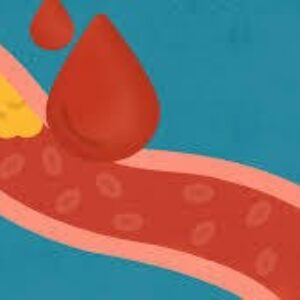

علاوه بر حمله قلبی، عوارض جدی دیگری نیز در اثر عدم درمان کلسترول “بد” وجود دارد.

تصلب شرایین، که تجمع پلاک در سراسر بدن است